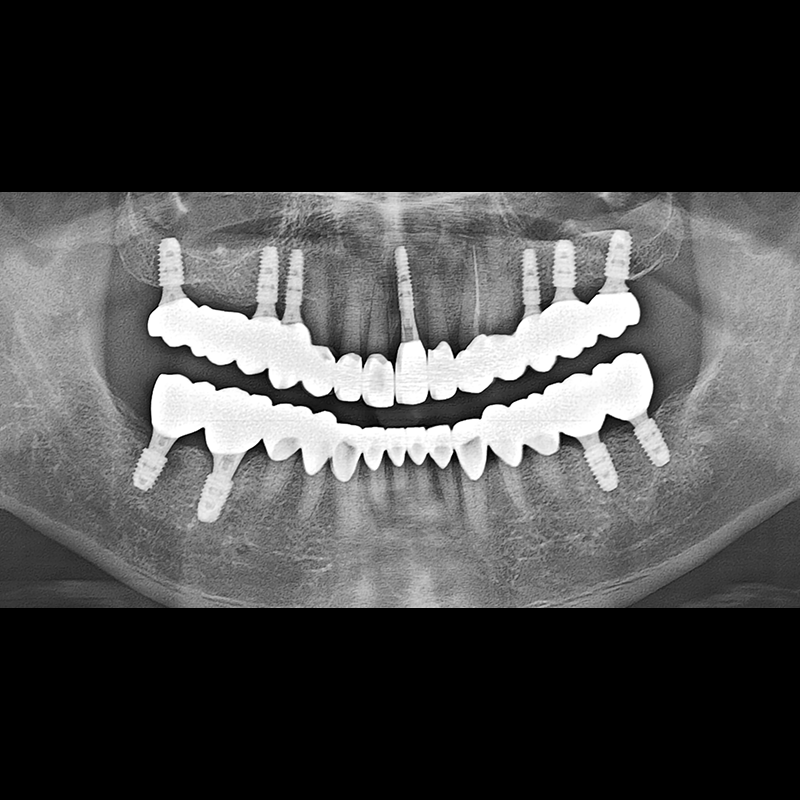

BEFORE AFTER

インプラント手術事例 2025.05.30

欠損した歯の部分と、生かしにくい歯の位置にインプラントを植立しました。